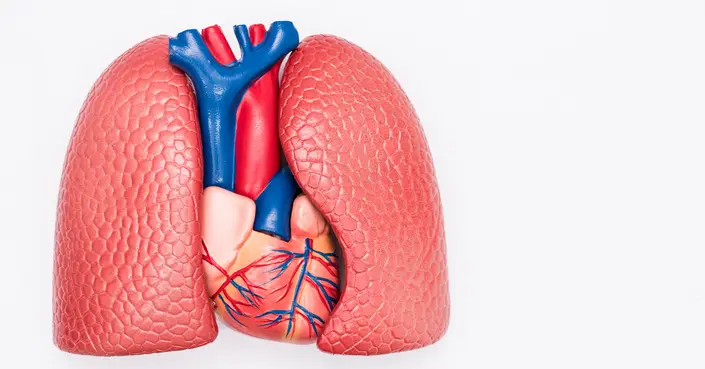

تؤدي الرئتان دورًا حيويًا في حياتنا، فهما محرك جسمنا الذي يزوده بالأكسجين الضروري. لكن ماذا يحدث عندما تتوقف إحدى الرئتين أو جزء منها عن العمل بكفاءة؟ هذا ما يعرف بضمور الرئة، أو ما يُسمى طبيًا بانخماص الرئة (Atelectasis). إنها حالة خطيرة تتطلب فهمًا عميقًا لأسبابها وأعراضها وطرق علاجها.

ما هو ضمور الرئة (انخماص الرئة)؟

ضمور الرئة، المعروف أيضًا بانخماص الرئة (Atelectasis)، هو انهيار جزئي أو كلي لإحدى الرئتين أو جزء منها. يحدث هذا عندما لا تتمدد الحويصلات الهوائية الصغيرة داخل الرئة بشكل كامل أثناء الشهيق.

يمكن أن تتطور هذه الحالة بسرعة كبيرة في غضون دقائق، أو تظهر تدريجيًا على مدى أيام أو أسابيع. يُعد ضمور الرئة خطرًا على حياة المصابين، خاصة الأطفال الصغار أو الأشخاص الذين يعانون من مشاكل صحية سابقة في الرئة.

من المهم الإشارة إلى أن ضمور الرئة يختلف عن “الرئة المنهارة” أو الاسترواح الصدري (Pneumothorax)، حيث يشير الأخير إلى تسرب الهواء بين الرئة وجدار الصدر، مما يسبب انهيار الرئة، بينما ضمور الرئة هو انهيار الحويصلات الهوائية نفسها.